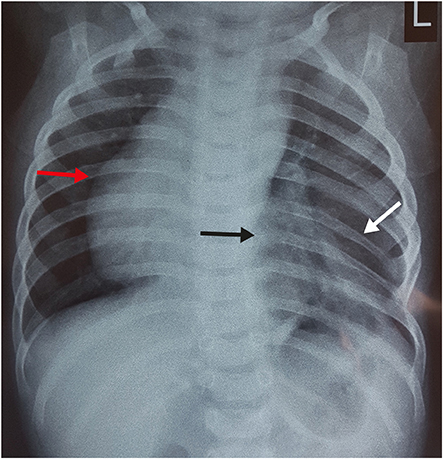

A plain radiograph chest X-ray (Fig. 1) was suspicious of bowel loops or stomach herniating into the left hemithorax. With a working diagnosis of congenital diaphragmatic hernia (CDH)/hiatus hernia, the patient was planned for emergency surgery. The patient was explored through a left subcostal incision. There was no diaphragmatic defect. Although the left diaphragm was higher up in position, it was normal, thick and muscular and not thin and redundant, as in diaphragmatic eventration. There was no paraesophageal or sliding hernia. The spleen was found to be free from its ligamentous attachments. On palpation, of the left chest wall, the lower ribs and costal cartilages were absent along with a portion of the lower sternum. There were deficiency and absence of attachment of pectoral muscles in that region creating a 4×3 cm size muscular defect, which was repaired with non-absorbable sutures. The post-operative period was uneventful and the child was discharged 5 days later. During follow up, the child was evaluated with CT chest with 3D reconstruction (Fig. 2) which was suggestive of dextrocardia, partially fused left 5th and 6th ribs, hypoplastic 7th and 8th ribs, left lung smaller in volume as compared to the right lung, sternal defect and scoliosis of the dorso-lumbar spine. To rule out any associated syndromic conditions, ultrasound (USG) of kidney, ureter, bladder (KUB), 2-dimensional (2D) echocardiography (ECHO) and gastroesophageal reflux (GER) scan were done, which were normal. The child was doing well during the last follow up at 8 months age.

Fig. 2

Computerized tomography with 3-dimensional reconstruction showing hypoplastic 7th and 8th rib (A, black arrow), fused 5th and 6th ribs (B, black arrow), dextrocardia (C, black arrow) and costal cartilage defect (C, white arrow).

Fig. 2 Computerized tomography with 3-dimensional reconstruction showing hypoplastic 7th and 8th rib (A, black arrow), fused 5th and 6th ribs (B, black arrow), dextrocardia (C, black arrow) and costal cartilage defect (C, white arrow).